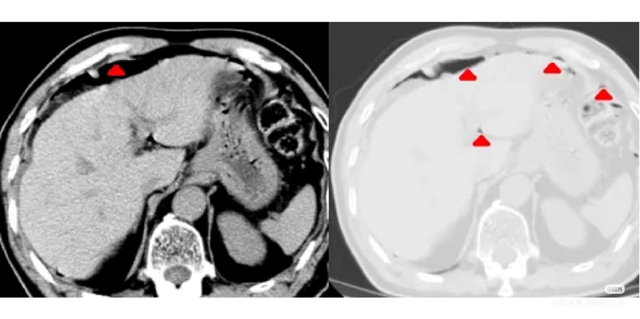

近日,我院放射科凭借精准的CT影像诊断,为一名胃肠穿孔引发气腹的急诊患者赢得宝贵治疗时间。 12月3日,66岁的马先生因腹痛到院就诊,急诊行全腹CT平扫检查。放射科徐柱荣副主任医师在阅片时敏锐发现,患者双侧膈下、胆囊窝、肝脾外缘旁、肝肾隐窝及盆腔等部位,均可见弧形、点状、短条状气体密度影,胃肠道内伴有少量液平面,当即确诊为胃肠穿孔并全腹腹水。考虑到病情凶险,需及时准确的诊断以指导后续治疗,放射科第一时间报危机值给主管医生,为...